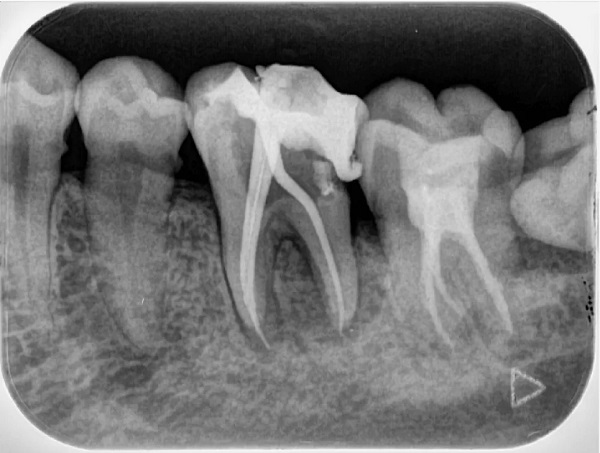

Chụp X quang 01 răng

Phương pháp chụp X quang 01 răng là một kỹ thuật phổ biến để xác định vị trí chính xác của răng bị tổn thương và tình trạng của các răng xung quanh. Dịch vụ này thường được sử dụng trong các trường hợp như răng sâu, cần trám răng, lấy tủy răng và các dịch vụ khác liên quan đến răng.

Chụp X quang 01 răng giúp xác định tổn thương ở răng